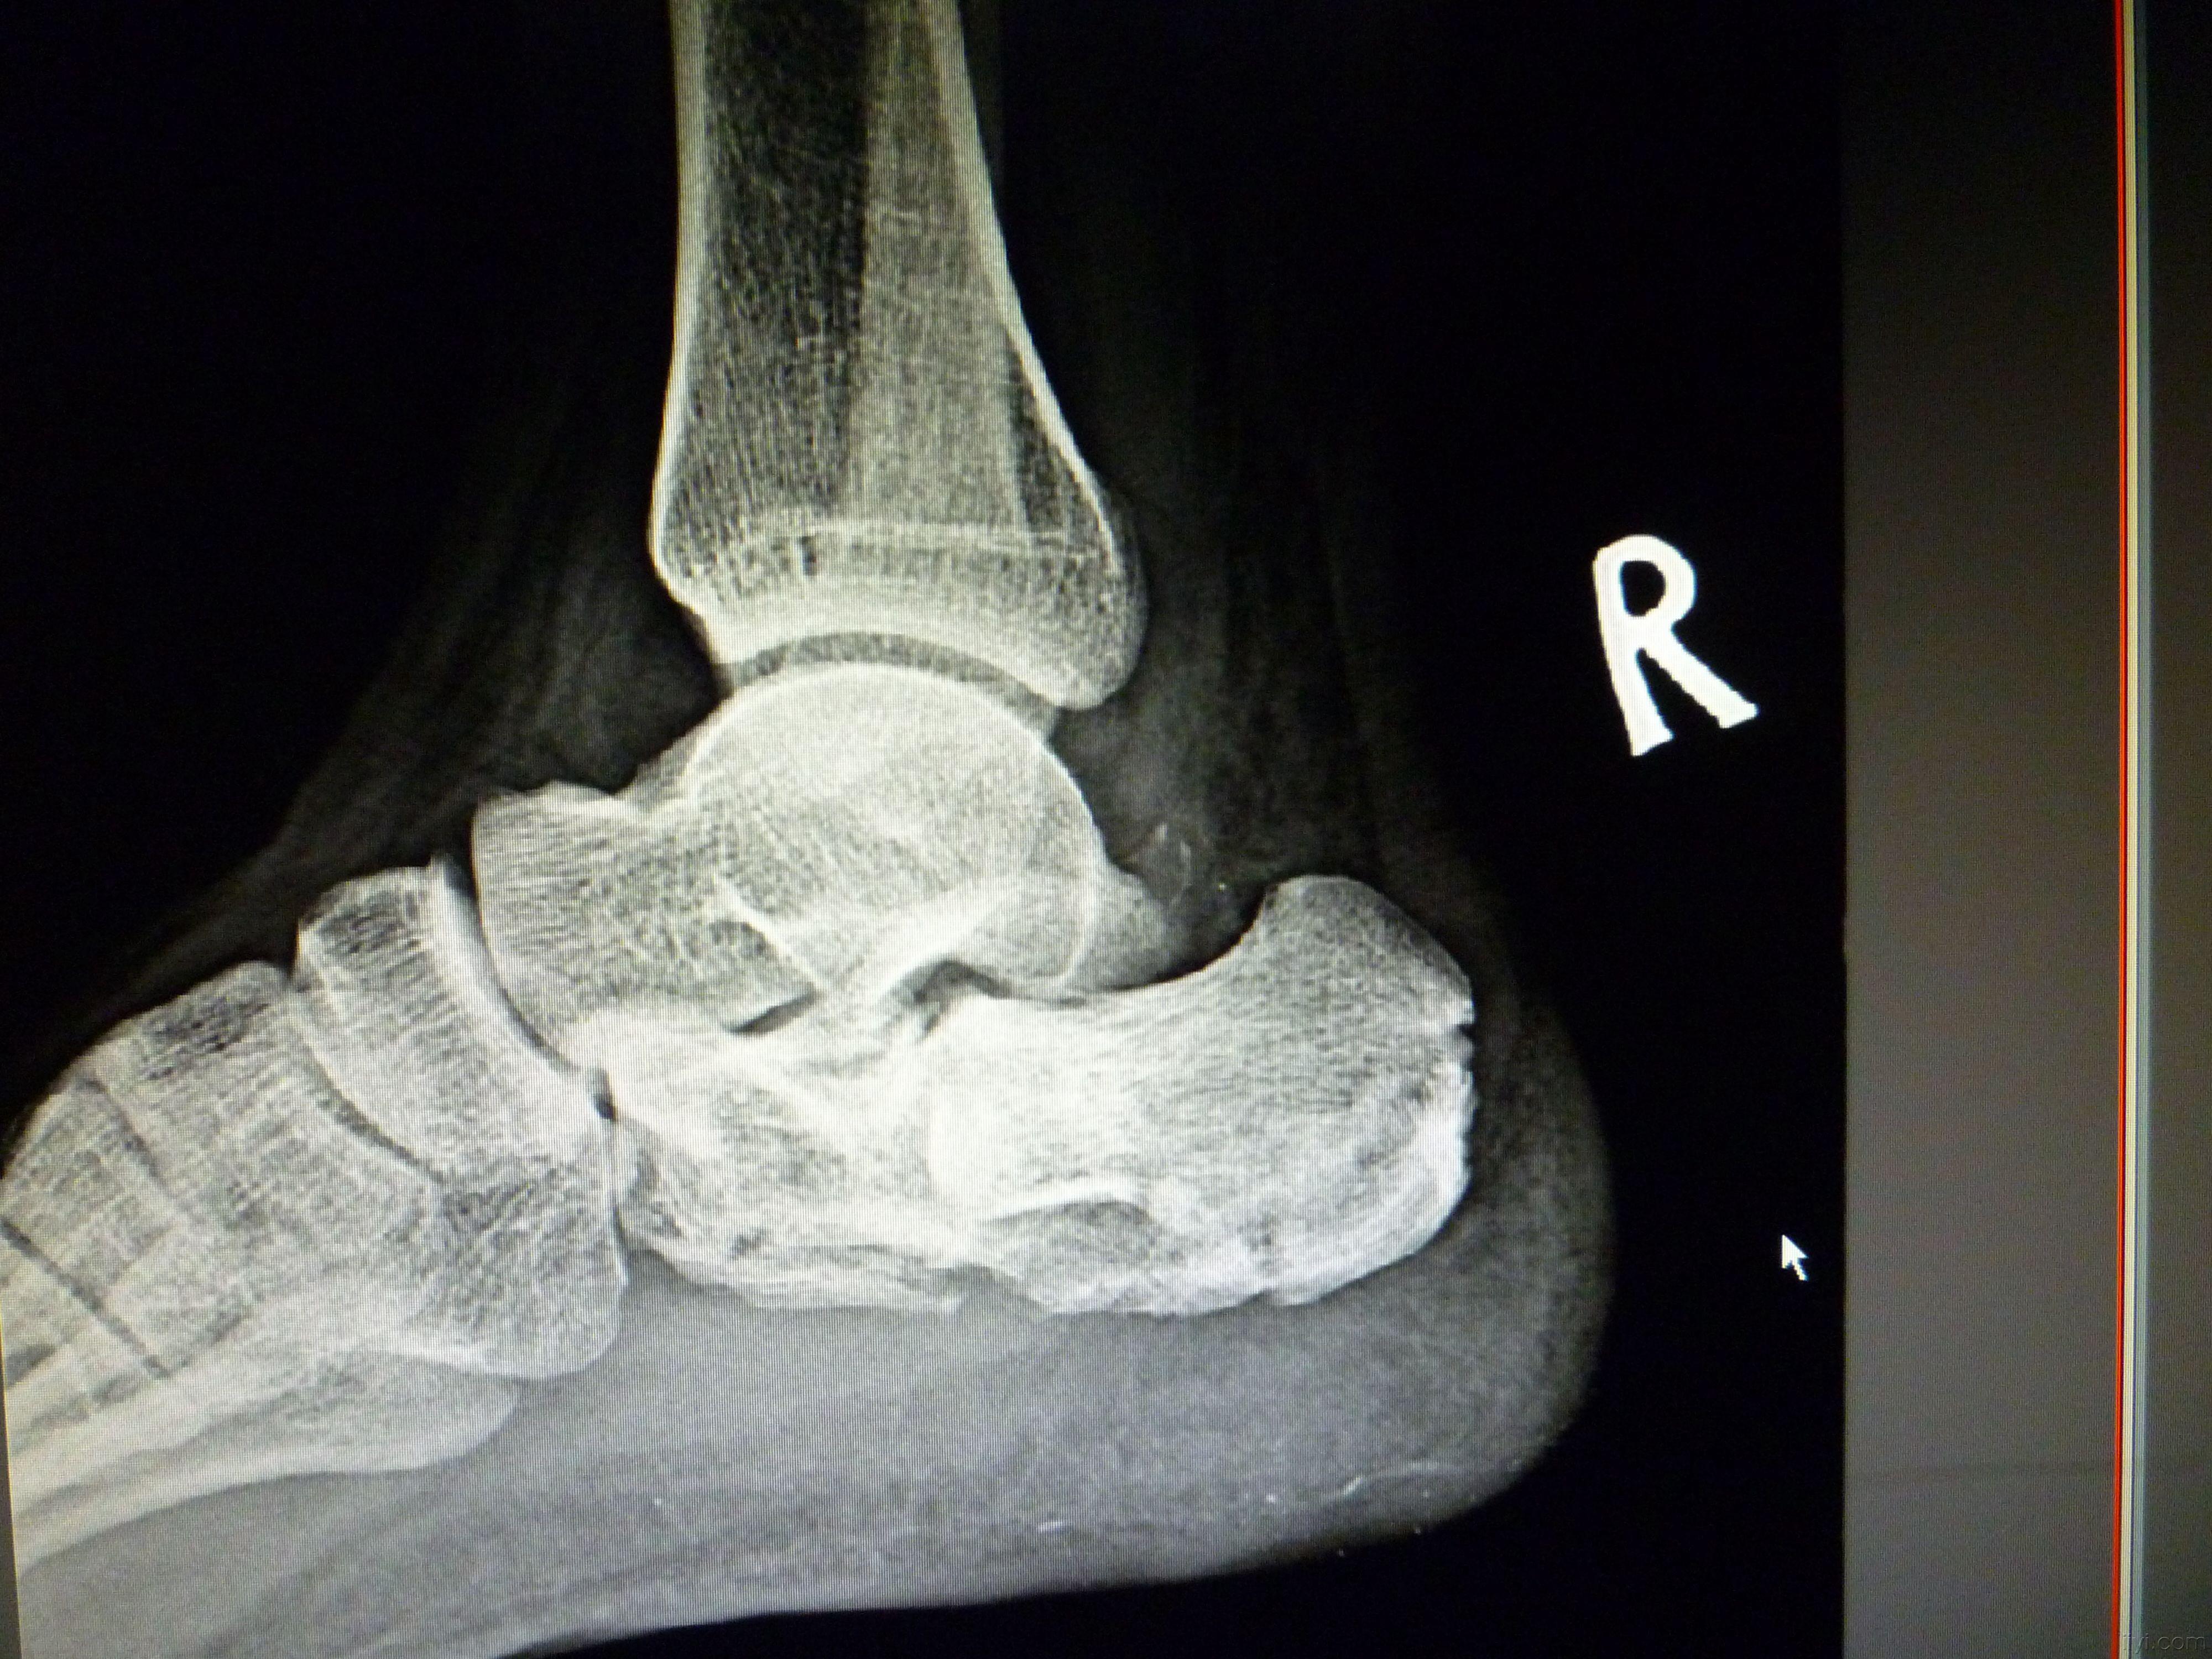

右跟骨骨折

跟骨骨折

请大家分析下跟骨有没有骨折